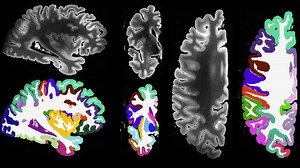

Mayo Clinic 7-Tesla MRI scanner i…

YouTubeMayo Clinic